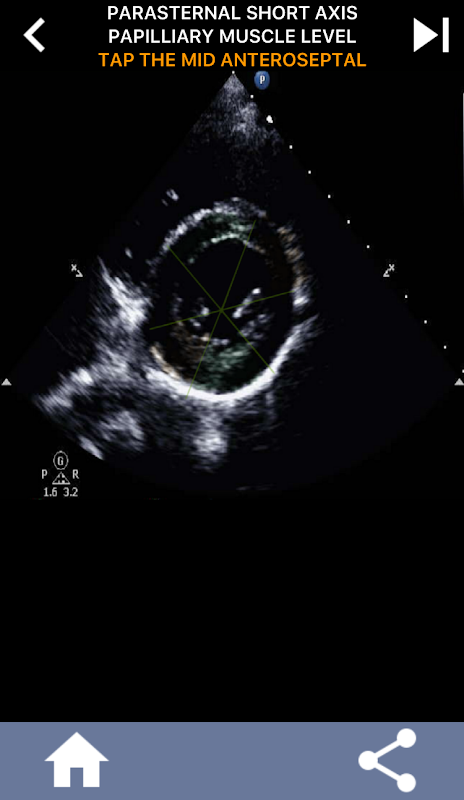

AHA 심장 세그먼트 학습을 위한 퀴즈 기반의 시각적 접근 방식: 심초음파

AHA(미국 심장 협회) 심장 세그먼트를 이해하는 것은 심장 초음파 기사가 보고서를 작성하는 심장 전문의와 효과적으로 의사 소통하는 데 가장 중요합니다. 특정 해부학적 부위와 해당 부분을 알면 소노그래퍼는 모든 이상 또는 발견 사항을 정확하게 설명하고 전달할 수 있으므로 두 전문가 간의 명확하고 간결한 커뮤니케이션이 보장됩니다.

이러한 이해는 심장 전문의가 문제의 정확한 위치를 확인하려고 하거나 당직 의사가 특정 영역 내에서 문제를 식별하여 소노그래퍼가 중하벽과 같은 해당 부분을 정확하게 표시하도록 유도할 때 특히 중요합니다. 따라서 AHA 심장 부분을 포괄적으로 파악하는 것이 필수 기술입니다.

이 앱은 실제 에코 이미지를 사용하여 여러분의 지식을 테스트할 것입니다. 저는 종종 이것이 최고의 교육 방법이라고 생각합니다.